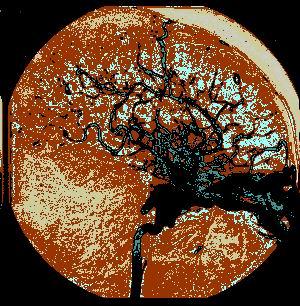

问题 病历摘要:??患者女性,25岁。10日前因车祸致头部外伤,伤后有短暂昏迷史,右鼻腔少量血性液体流出。8日前开始感颅内有杂音。7日前右眼睑出现肿胀伴右眼视力下降,并逐渐加重。既往体健。体检:神志清楚,右眼明显突出并有搏动,右眼睑及球结膜水肿充血,眼球部及颞部可听到与脉搏一致的隆隆样杂音。瞳孔右大于左(5:3mm),视力右眼失明,右眼球各方向运动均受限,左眼视力及运动正常。 对明确诊断有决定性价值的辅助检查是哪种?

选项 A.脑血管造影 B.TCD C.CT D.MR E.颅骨平片 F.诱发电位 G.PET H.SPECT I.脑磁图

答案 A